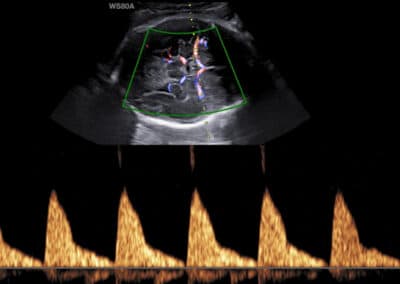

Dopplerovské vyšetření trojcípé srdeční chlopně – normální nález

Dopplerovské vyšetření trojcípé srdeční chlopně – trikuspidální regurgitace

UZ vyšetření trojcípé chlopně dle FMF protokolu

Protokol pro správné vyšetření trojcípé chlopně:

CRL 45-84 mm (11-13+6 týden) Zvětšení (hrudník vyplňuje většinu obrazovky) Apikální čtyřdutinová projekce (hrot srdce směřuje směrem nahoru, ev. dolů na obrazovce) Gate 3mm přes trikuspidální chlopeň Odklon toku krve přes chlopeň 0-30º od vertikální osy Vysoká rychlost posunu křivky (2-3cm/s) Opakovat měření minimálně 3x Regurgitace na trojcípé chlopni je přítomna, pokud trvá minimálně polovinu systoly a její rychlost je vyšší než 60 (80) cm/s